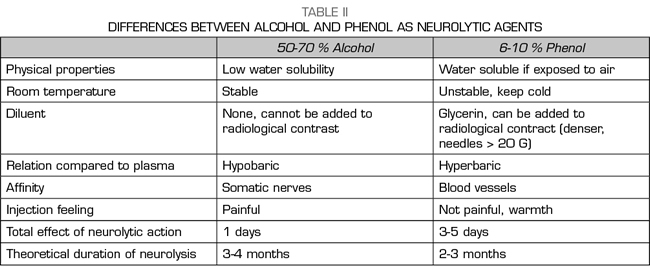

NEUROLISIS WITH ALCOHOL OR WITH PHENOL?

Alcohol and phenol are the two agents used for the chemical neurolysis of the sympathetic chain (62). Ethyl alcohol is a colorless and hypobaric solution compared to plasma, diluting it to 50-70% to obtain a sympatholytic effect. Phenol is not marketed in Spain and it must be previously prepared in the hospital pharmacy. Phenol is unstable at room temperature and its half-life is 1 year when it is kept cold and away from light. It is usually used at concentrations of 6-10% for sympathetic blockages, since below 2% it only produces an anesthetic effect and above 20% it can destroy somatic nerves. The chemical properties and differences between both agents are summarized in Table II.

Studies comparing alcohol with phenol in sympathetic blockages are scarce. Koyyalagunta et al. (63) published a retrospective study of 93 abdominal cancer patients undergoing chemical neurolysis of the splanchnic nerves, assessing the effectiveness, duration of blockage and adverse effects of both agents. They found no differences in pain relief or the incidence of complications. Tumor infiltration of the celiac trunk and previous radiotherapy did not interfere with the effectiveness of the procedure, which is why the researchers chose the splanchnic nerves as the target.

There is a large literature variety about what type of agent to use and how much volume to administer, basically depending on the target chosen, the percutaneous approach, and the imaging technique we use. For blockages performed transcrurally, about 15-20 ml of neurolytic agent is recommended on each side, with alcohol being preferred because of its lower affinity for blood vessels. For the abdominal ultrasound approach, 8-10 ml of alcohol is sufficient. For the neurolysis of the splanchnic nerves, 6-8 ml of phenol is recommended, due to its lower affinity for the somatic nerves. If we use the endoscopic ultrasound technique, the volume is also low. LeBlanc et al. (64) found no differences between the endoscopic ultrasound administration of 20 ml versus 10 ml of alcohol.